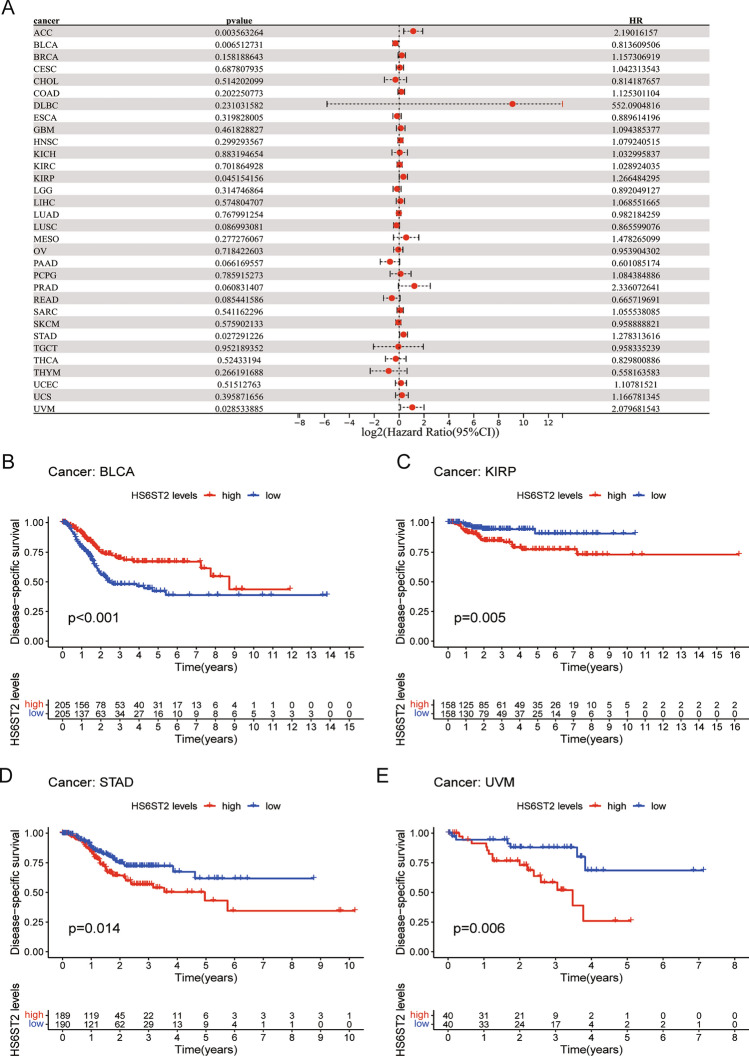

Prognostic significance of HS6ST2

Via the TCGA database, we examined the value of HS6ST2 mRNA expression for predicting OS, DFI, DSS, and PFI across cancers. Cox regression analysis revealed that low HS6ST2 expression was connected with poorer OS in breast invasive carcinoma, mesothelioma, kidney renal clear cell carcinoma, uveal melanoma, and adrenocortical carcinoma but associated with better OS in rectum adenocarcinoma and bladder urothelial carcinoma (Fig. 3A). As determined by KM OS analysis, HS6ST2 was a protective factor for patients with bladder urothelial carcinoma and rectum adenocarcinoma but a risk factor for patients with kidney renal papillary cell carcinoma and uveal melanoma (Fig. 3B–E). We also determined the correlation between the expression of HS6ST2 and the DFS rate in 33 different cancers. HS6ST2 was found to be a protective factor in bladder urothelial carcinoma and a risk factor in kidney renal papillary cell carcinoma, stomach adenocarcinoma, adrenocortical carcinoma, and according to Cox regression analyses (Fig. 4A). Similarly, KM analysis of DSS uncovered that HS6ST2 was a risk factor in stomach adenocarcinoma, kidney renal papillary cell carcinoma, and uveal melanoma but acted as a protective factor in bladder urothelial carcinoma (Fig. 4B–E).